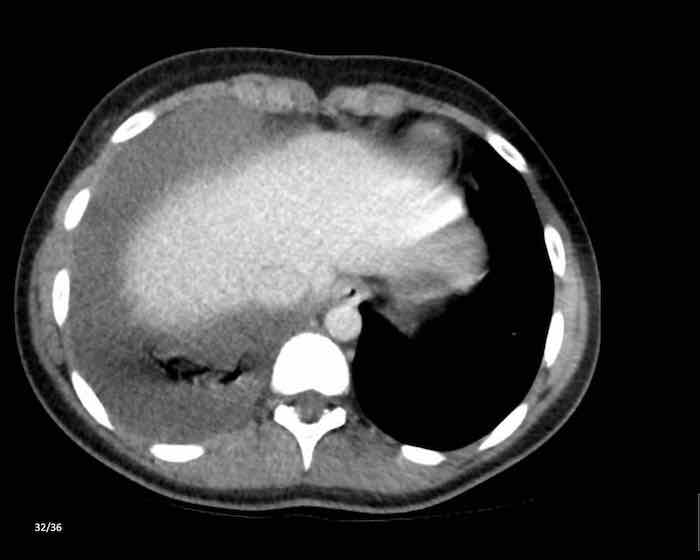

Các hình ảnh này của một phụ nữ 65 tuổi có tiền sử mắc bệnh Graves, một rối loạn tự miễn liên quan đến tình trạng cường chức năng tuyến giáp.

CT được thực hiện vì lý do ho ra máu.

Hình ảnh

Có một tuyến ức to lớn, cồng kềnh chứa mô mỡ đại thể.

Đây là hình ảnh điển hình của tăng sản tuyến ức.

Tăng sản tuyến ức trong bệnh Graves có liên quan đến tình trạng dư thừa hormone tuyến giáp và kháng thể kháng thụ thể thyrotropin.

Tình trạng này thường cải thiện sau khi điều trị thành công bệnh Graves.